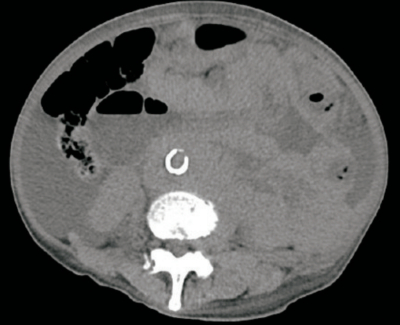

血液所見:赤血球 345万、Hb 9.2 g/dL、Ht 28%、白血球 9,000、血小板 9.5万。血液生化学所見:総蛋白 5.2 g/dL、アルブミン 2.7 g/dL、総ビリルビン 0.6 mg/dL、AST 24 U/L、ALT 13 U/L、LD 1,120 U/L (基準 120〜245) 、尿素窒素 28 mg/dL、クレアチニン1.7 mg/dL、尿酸10.2mg/dL。腹部単純CTを別に示す。